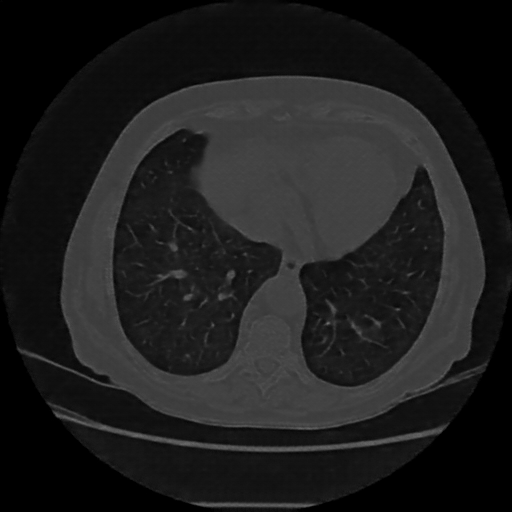

Reconstructed NATIVE CT scan (cycle consistency)

Full window (WL 1023.5, WW 4095 β†’ Low βˆ’1024, High +3071)

Lung window (WL -600, WW 1500 β†’ Low βˆ’1350, High +150)

Mediastinum window (WL 40, WW 400 β†’ Low βˆ’160, High +240)